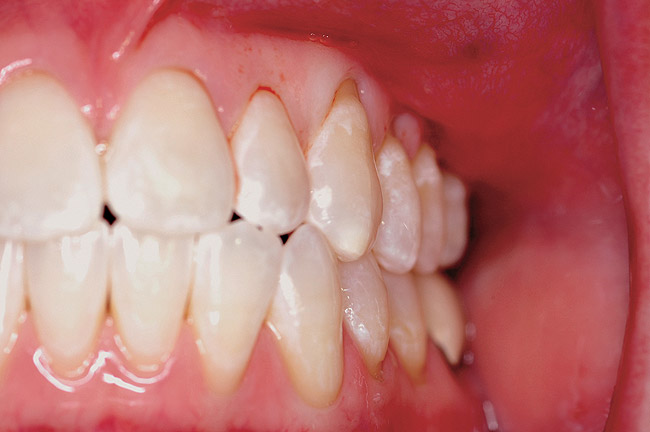

The patient presented with gingival recession and a complaint of cold sensitivity in the maxillary first and second bicuspid teeth (Figure 14). Minimal attached gingiva was noted. A connective tissue graft was placed to widen the band of attached gingiva and eliminate the cold sensitivity present presurgically (Figure 15).

Figure 14  Gingival recession on the first and second maxillary premolars with a thin band of attached gingiva.

Figure 14

Figure 15   Correction of the attached gingiva and repair of the recession shown 8 weeks postsurgery.

Figure 15